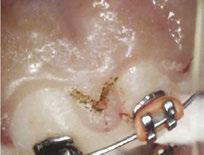

Dr. Bill Waggoner discusses the benefits of using liners along with a case presentation from Dr. Paul Bahn

Cavity liners and indirect pulp capping (IDPC) materials have been used in dentistry for decades. The recent introduction of NuSmile’s NeoLINER™ LC now provides one of the most therapeutic, easy-to-use liners on the market! It is a light-cured MTA-modified bioactive material that is recommended for use as either a cavity liner or as an indirect pulp-capping material. For decades, calcium hydroxide was the most popular lining or indirect pulp-capping material, primarily because of its ability to stimulate reparative dentin. However, its solubility after placement was found to be a problem. Zinc oxide and eugenol, glass ionomers, and resin-modified glass ionomers have also been used as liners, bases, and IDPC materials, but each has shortcomings.

Liners are materials that are placed in thin layers over exposed dentin in the deepest portion of cavity preparations. They function to seal dentin tubules, prevent microleakage, provide some thermal insulation, and depending on the material used, stimulate the formation of reparative or tertiary dentin. Historically, indirect pulp-capping materials have been used when a thin layer of carious dentin remains after deep excavation with no exposure of the pulp and no clinical signs of irreversible pulpitis. In recent years, indirect pulp capping in pediatric dentistry has been utilized when larger amounts of carious tissue remain, but the caries can be sufficiently sealed from the oral environment with a full coverage restoration like a stainless steel or zirconia crown. The main goal of both liners and IDPC materials is to minimize inflammation, promote healing, and maintain vitality of the dental pulp. Indirect pulp capping materials may also demonstrate some bactericidal properties to kill any remaining bacteria that may remain.

The MTA in NuSmile’s NeoLINER LC provides a continuous high calcium release. This, in combination with a high pH, promotes hydroxyapatite formation and protects against hypersensitivity. The high pH also has bactericidal effects to reduce remaining bacteria. NeoLINER LC is packaged in a syringe with 27-gauge disposable tips that allow for precise and easy placement. Its viscosity ensures it will stay in the area where it is placed until it is cured with a curing light. NeoLINER LC is

moisture tolerant, has low water solubility, and is compatible with all etching, bonding, and resin restorative materials. It’s also radiopaque for easy postoperative assessment.

While it is an excellent liner and IDPC material, NeoLINER LC is not recommended for direct pulp capping because of its resin component which can act as an irritant. Any materials containing a resin can damage or kill pulpal tissue if placed in direct contact. If a pulpal exposure is realized, a resin-free MTA material such as NuSmile’s NeoMTA® 2 or NeoPUTTY® is recommended as a direct pulp-capping agent due to its exceptional biocompatibility. These MTA materials, which have a delayed set, may be covered with NeoLINER LC for placement of an immediate final restoration.

Figure 1: Preoperative periapical radiograph of tooth No. 30 with a large radiolucent lesion approximating the distal pulpal horn and a smaller radiolucent lesion closer to the mesial marginal ridge Figure 3: Conservative removal of all carious dentin on all axial walls and pulpal floor. No clinical pulpal exposure noted, but likely very close to distal buccal pulp horn Figure 2: Large active carious lesion involving the entire distal buccal cusp and surrounding aspect of tooth No. 30. Smaller Class VI lesion located on the mesial lingual cusp on No. 30 Figure 4: Placement and curing of two separate thin layers of NeoLINER over the dentin. Image depicts the NeoLINER following the indirect pulp cap of tooth No. 30